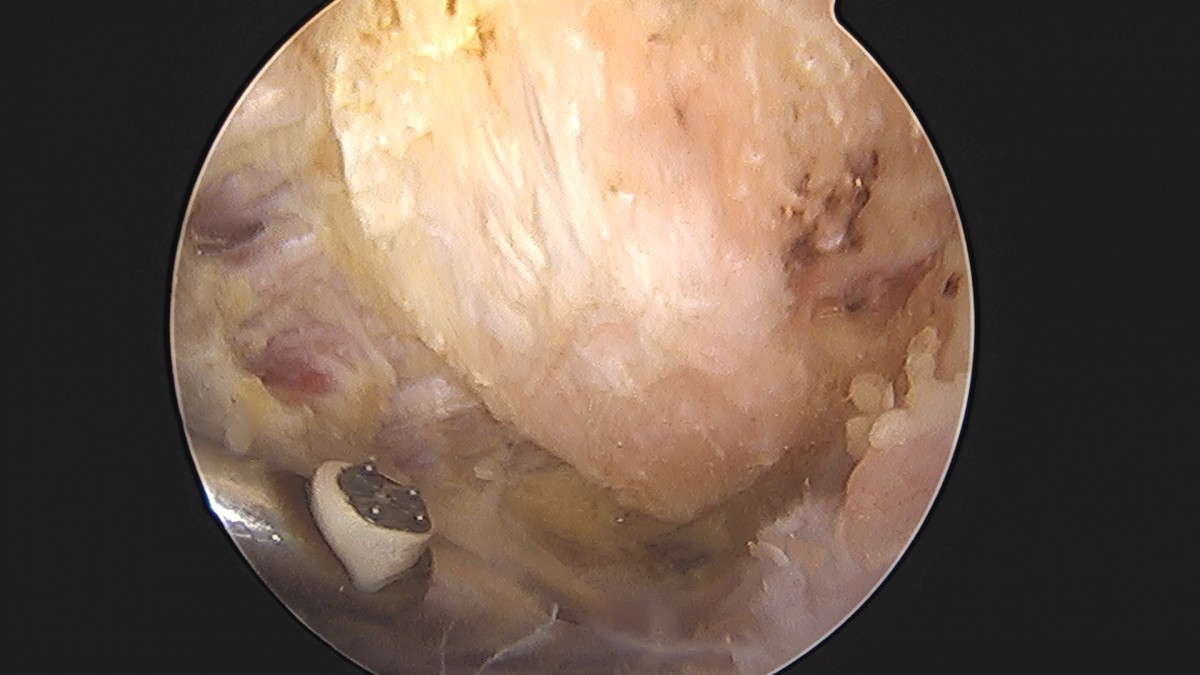

이재상원장님 어깨 견봉하 감압술 및 석회 제거술 이형O 환자

작성자 최고관리자 댓글 0건 조회 746회 작성일 25-09-16 15:40